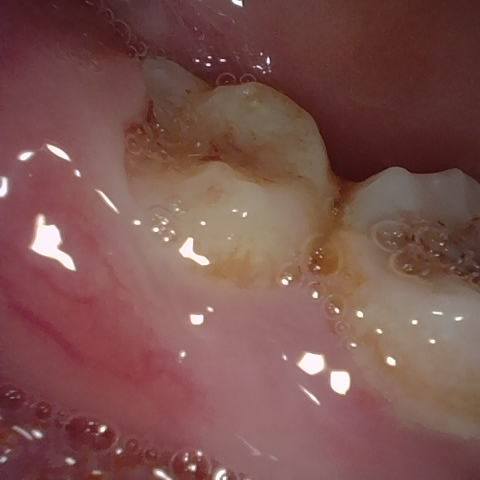

NHD11140

Annotated as "Good"